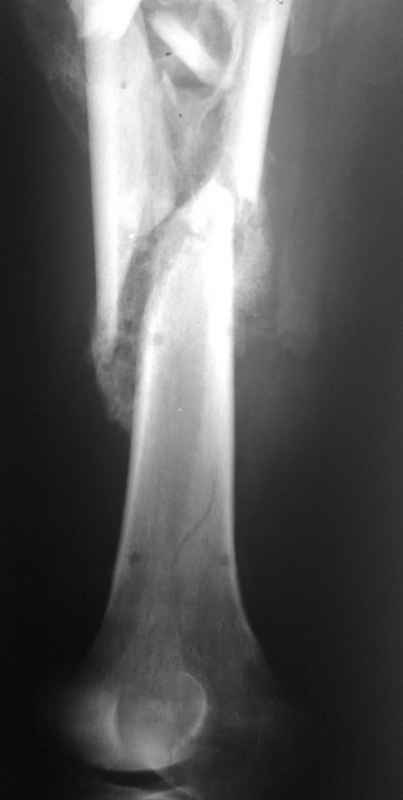

Re: Неправильно срастающийся оскольчатый перелом бедра

Спасибо за снимки. Предложения по тактике прежние.